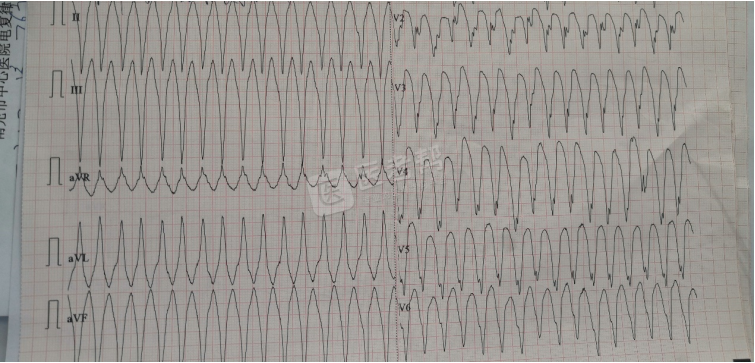

室性心动过速:连续3次或3次以上的室性期前收缩,频率大多为150~250次/min,节律大致规则,可略有不齐。QRS波群宽大畸形,时间≥0.12s,T波与QRS波群主波方向相反。房室分离,心室夺获与室性融合波。

Med怎么电写今年技能基地考试有这些变化,技能考试心电图部分知识点你都会吗?_https://www.jmylbn.com_新闻资讯_第8张